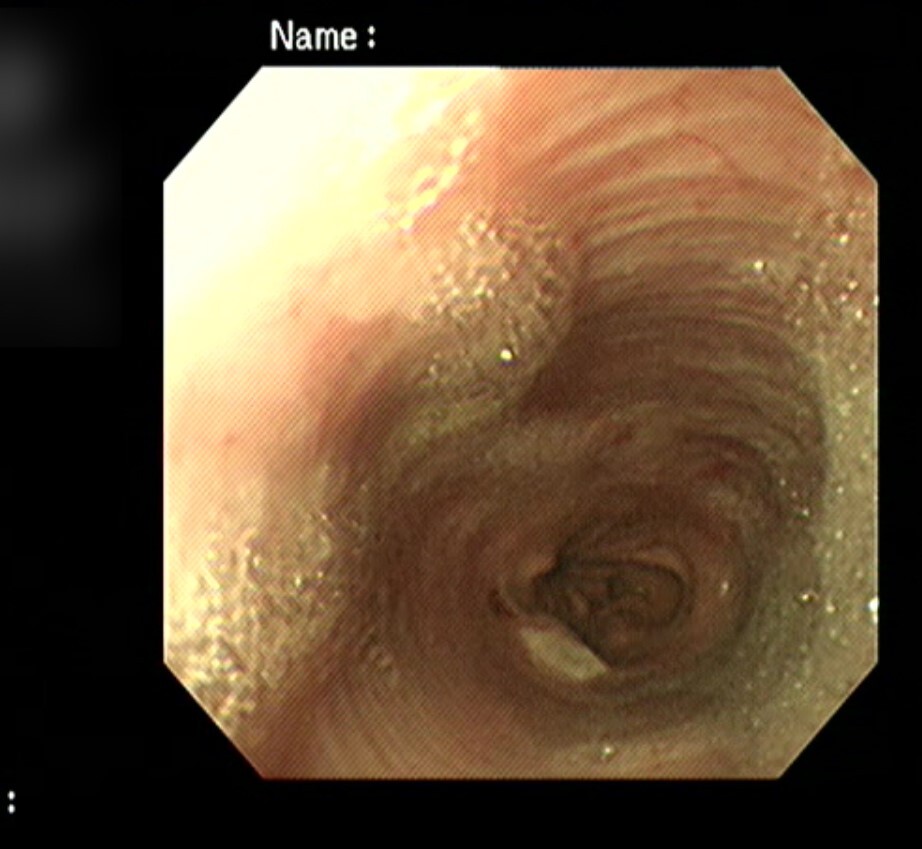

내시경 검사에서는 확장된 식도와

위-식도 연접 부위의 염증,

닫혀있어야 할 위-식도 연결 부위가

열린 상태로 위점막이 식도 내로 돌출되어

있는 것이 확인되었습니다.